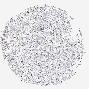

CANCER BREAST CANCER Show tissue menu

BRCA TCGA BRCA VALIDATION PROTEIN EXPRESSION